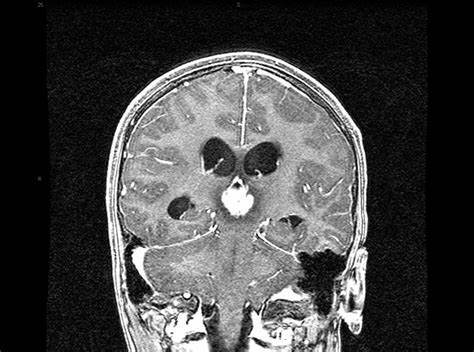

松果體腫瘤的臨床表現(xiàn)有哪些?

松果體腫瘤比較少見,一般多發(fā)于幼兒及青少年。頭痛、腦積水、視力障礙、聽力障礙等都是松果體腫瘤的臨床表現(xiàn)...

松果體瘤 是在松果體中形成的腫瘤。腺體是大腦中部的小腺體。它被你的大腦包圍。它產(chǎn)生一種稱為褪黑激素的激素,會影響您的睡眠-覺醒周期。松果體腫瘤是少見的腫瘤。它們...